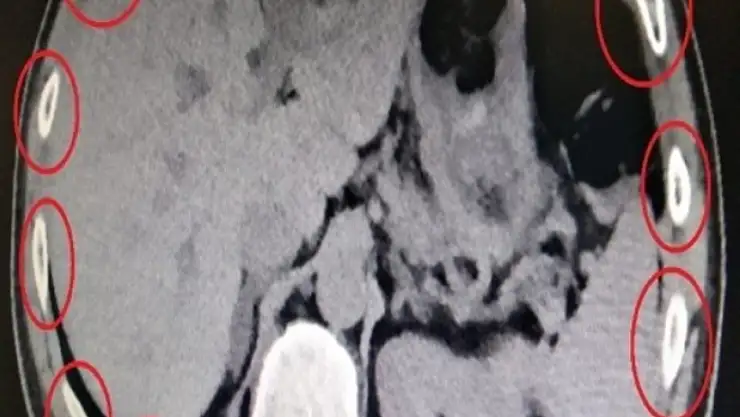

İl Emniyet Müdürlüğü Narkotik Suçlarla Mücadele Şubesi ekipleri, İran uyruklu bir kişinin üzerinde uyuşturucu getireceği bilgisi üzerine çalışma başlattı. Ekipler, Digor-Kars kara yolundaki denetim noktasında gerçekleştirilen uygulamada, daha önce takibe alınan İran uyruklu M.Z.T'yi yolcu otobüsünde yakaladı. Üst aramasında bir şey bulunamayan şüpheli, Kars Harakani Devlet Hastanesi'ne götürüldü. Burada çekilen röntgende İran uyruklu şüphelinin mide ve bağırsağında kapsüller halinde 7 parça halinde sentetik uyuşturucu olduğu belirlendi. Gözaltına alınan şüpheli, sevk edildiği adliyede çıkarıldığı hakimlikçe tutuklandı.